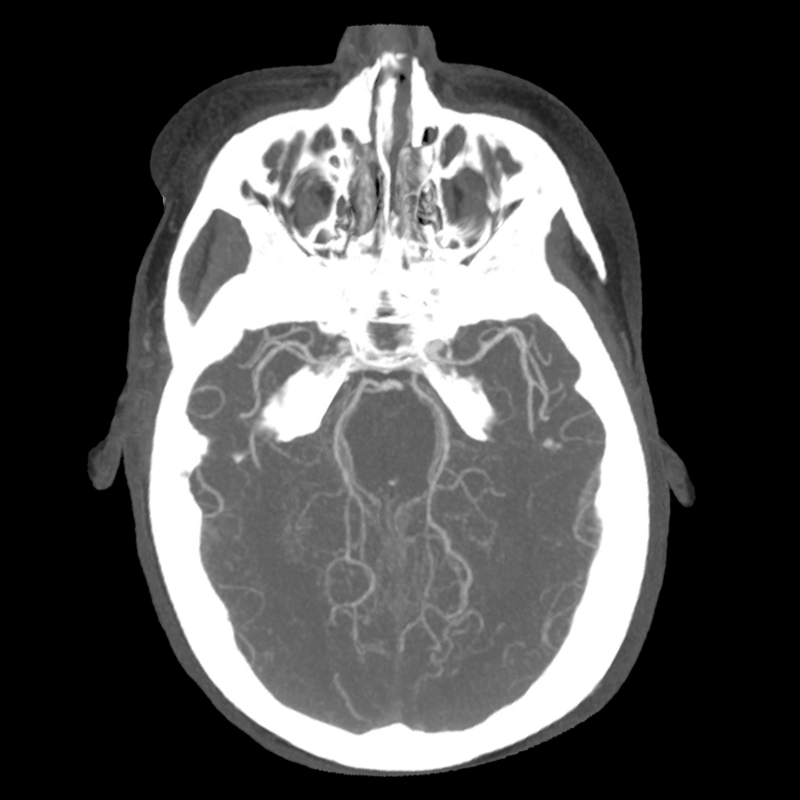

You arrive at the patient's room. You quickly examine her. Her left pupil is truly dilated and unreactive. Her right pupil is also dilated and unreactive, and also deviates to the right. She is unable to follow commands but is moving her extremities spontaneously. The right side of her body seems to be moving slightly less than her left. You escort the patient with RRT and your neurology colleague to radiology, where a non-contrast head CT and CTA head/neck are obtained.

CTA part 1 CTA part 2 CTA part 3

The non-contrast head CT looks generally similar to her prior scan. There's no new hemorrhage anywhere. There's no mass effect causing midbrain compression. The vessel imaging also looks unrevealing-- a slightly hypoplastic right A1 segment, but no clear LVO in either the anterior or posterior circulation. There's no vasoconstriction.